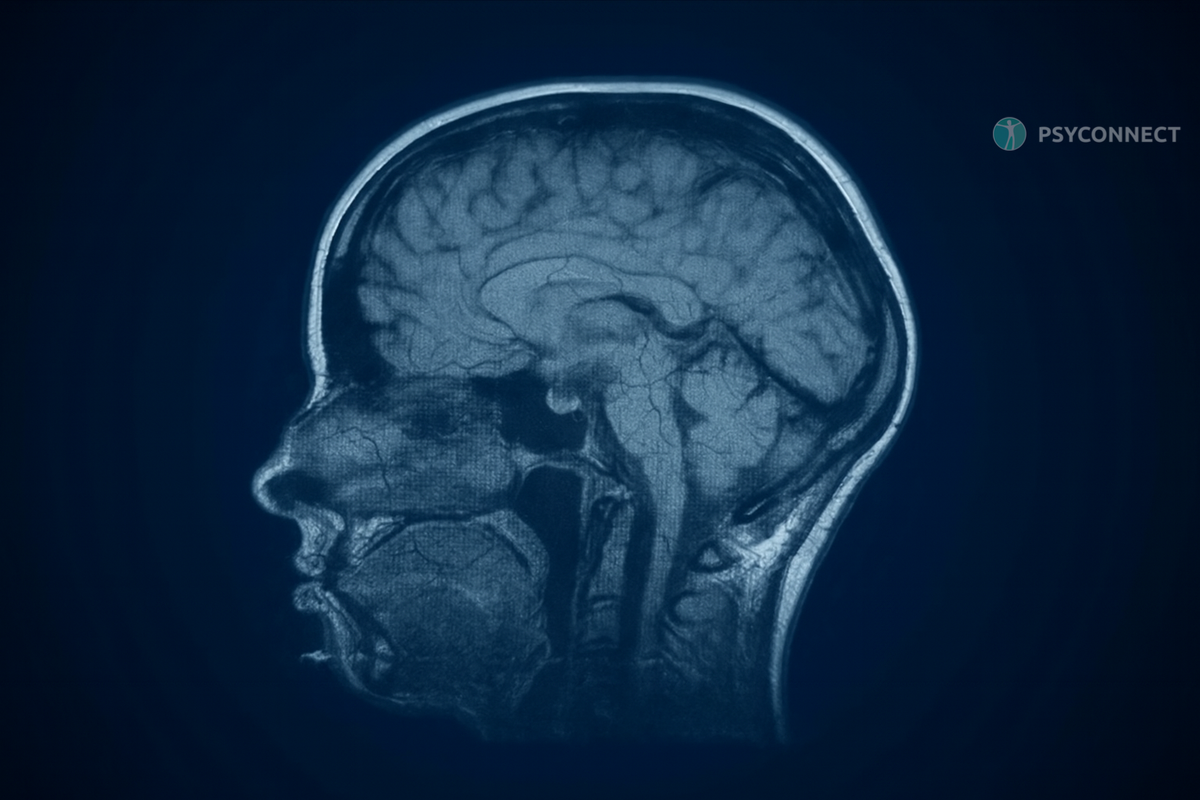

Последствия эмоционального насилия для мозга

Каждый день, просыпаясь, человек может чувствовать себя так, словно идет по тонкому льду. Простое слово или мимолетный взгляд способны вызвать панику. Хронический стресс, вызванный эмоциональным насилием, оказывает разрушительное воздействие на деятельность мозга.

- Искажение структуры мозга. Постоянный негативный фон формирует избыток гормонов стресса — схожих с кортизолом. Это приводит к уменьшению гиппокампа, отвечающего за память и обучение, и нарушает работу префронтальной коры, что затрудняет принятие решений.

- Гиперактивность миндалины. Центр страха в мозге становится чрезмерно активным, напоминая о себе постоянной тревогой и ощущением угрозы. Это состояние изматывает, заставляя нервничать при любых мелочах и придавая всему окружающему оттенок опасности.